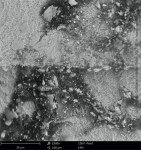

The actual manufacturing, sterilization, and packaging of a dental implant are largely underestimated factors that can affect the short- and long-term condition of the implant. How the implant is made and packaged can influence how surrounding bone interacts with the implant's surface during or after integration. The manufacturing process must be meticulous in all phases to ensure that the end-product is sterile and completely uncontaminated. Although the implant is sterile when removed from the package from the manufacturer, organic and/or non-organic particles on the implant's surface that are directly related to the manufacturing process may be present (Figure 1).11

In particular, organic carbonaceous foreign materials (Figure 2) have been associated with peri-implant bone loss and peri-implantitis.12 Exposure of bone to foreign particles activates macrophages to secrete pro-inflammatory cytokines, such as tumor necrosis factor-α, interleukin (IL)-1b, IL-6, and prostaglandin E2, which, in turn, stimulates the differentiation of osteoclast precursors into mature osteoclasts. The increased osteoclast activity associated with a foreign-body reaction may result in peri-implant bone resorption (Figure 3).13 Foreign materials 0.2 µm to 7.2 µm in size are especially classified as pro-inflammatory.14-16 If such particles detach from the implant surface during the implant insertion process, macrophages take up the particles by phagocytosis and subsequently release pro-inflammatory cytokines, which also leads to the expression of matrix metalloproteinase (MMP-8). The result is an expanding zone of soft-tissue damage and inflammation.13

Quality assessment studies on dental implants conducted by the CleanImplant Foundation in collaboration with Charité University in Berlin and the Sahlgrenska Academy in Gothenburg, Sweden, used scanning electron microscopy (SEM) to identify impurities on sterile-packaged dental implants. Findings of particulate contamination were reported for both titanium and zirconia (ceramic) implants specific to the process used during the manufacture and packaging of those implants.11,17 Reported data demonstrated that one out of three implant systems analyzed contained significant amounts of impurities that are technically avoidable. Those contaminants included organic particles from the manufacturing process, metallic particles of nickel, tungsten, iron, copper, and chromium from the milling or surface treatment process, and plastic from handling and packaging.

SEM images of titanium implants showed not only isolated spots of impurity, but also larger areas of the implant surface that were either insufficiently cleaned in the production process chain or contaminated without being noticed during packaging of the implants. Under high magnification in the SEMs, organic carbonaceous particles appeared as black spots (Figure 4 through Figure 7). The SEM images in low (500x) and high magnification (2,500x) revealed thermoplastic materials, synthetic polymers, and polysiloxanes on sterile implant surfaces. Ceramic implants also demonstrated organic debris related to manufacturing, as some that were analyzed following removal from the manufacturer's packaging exhibited large amounts of predominately organic carbonaceous residue when viewed under SEM (Figure 8 through Figure 11).17